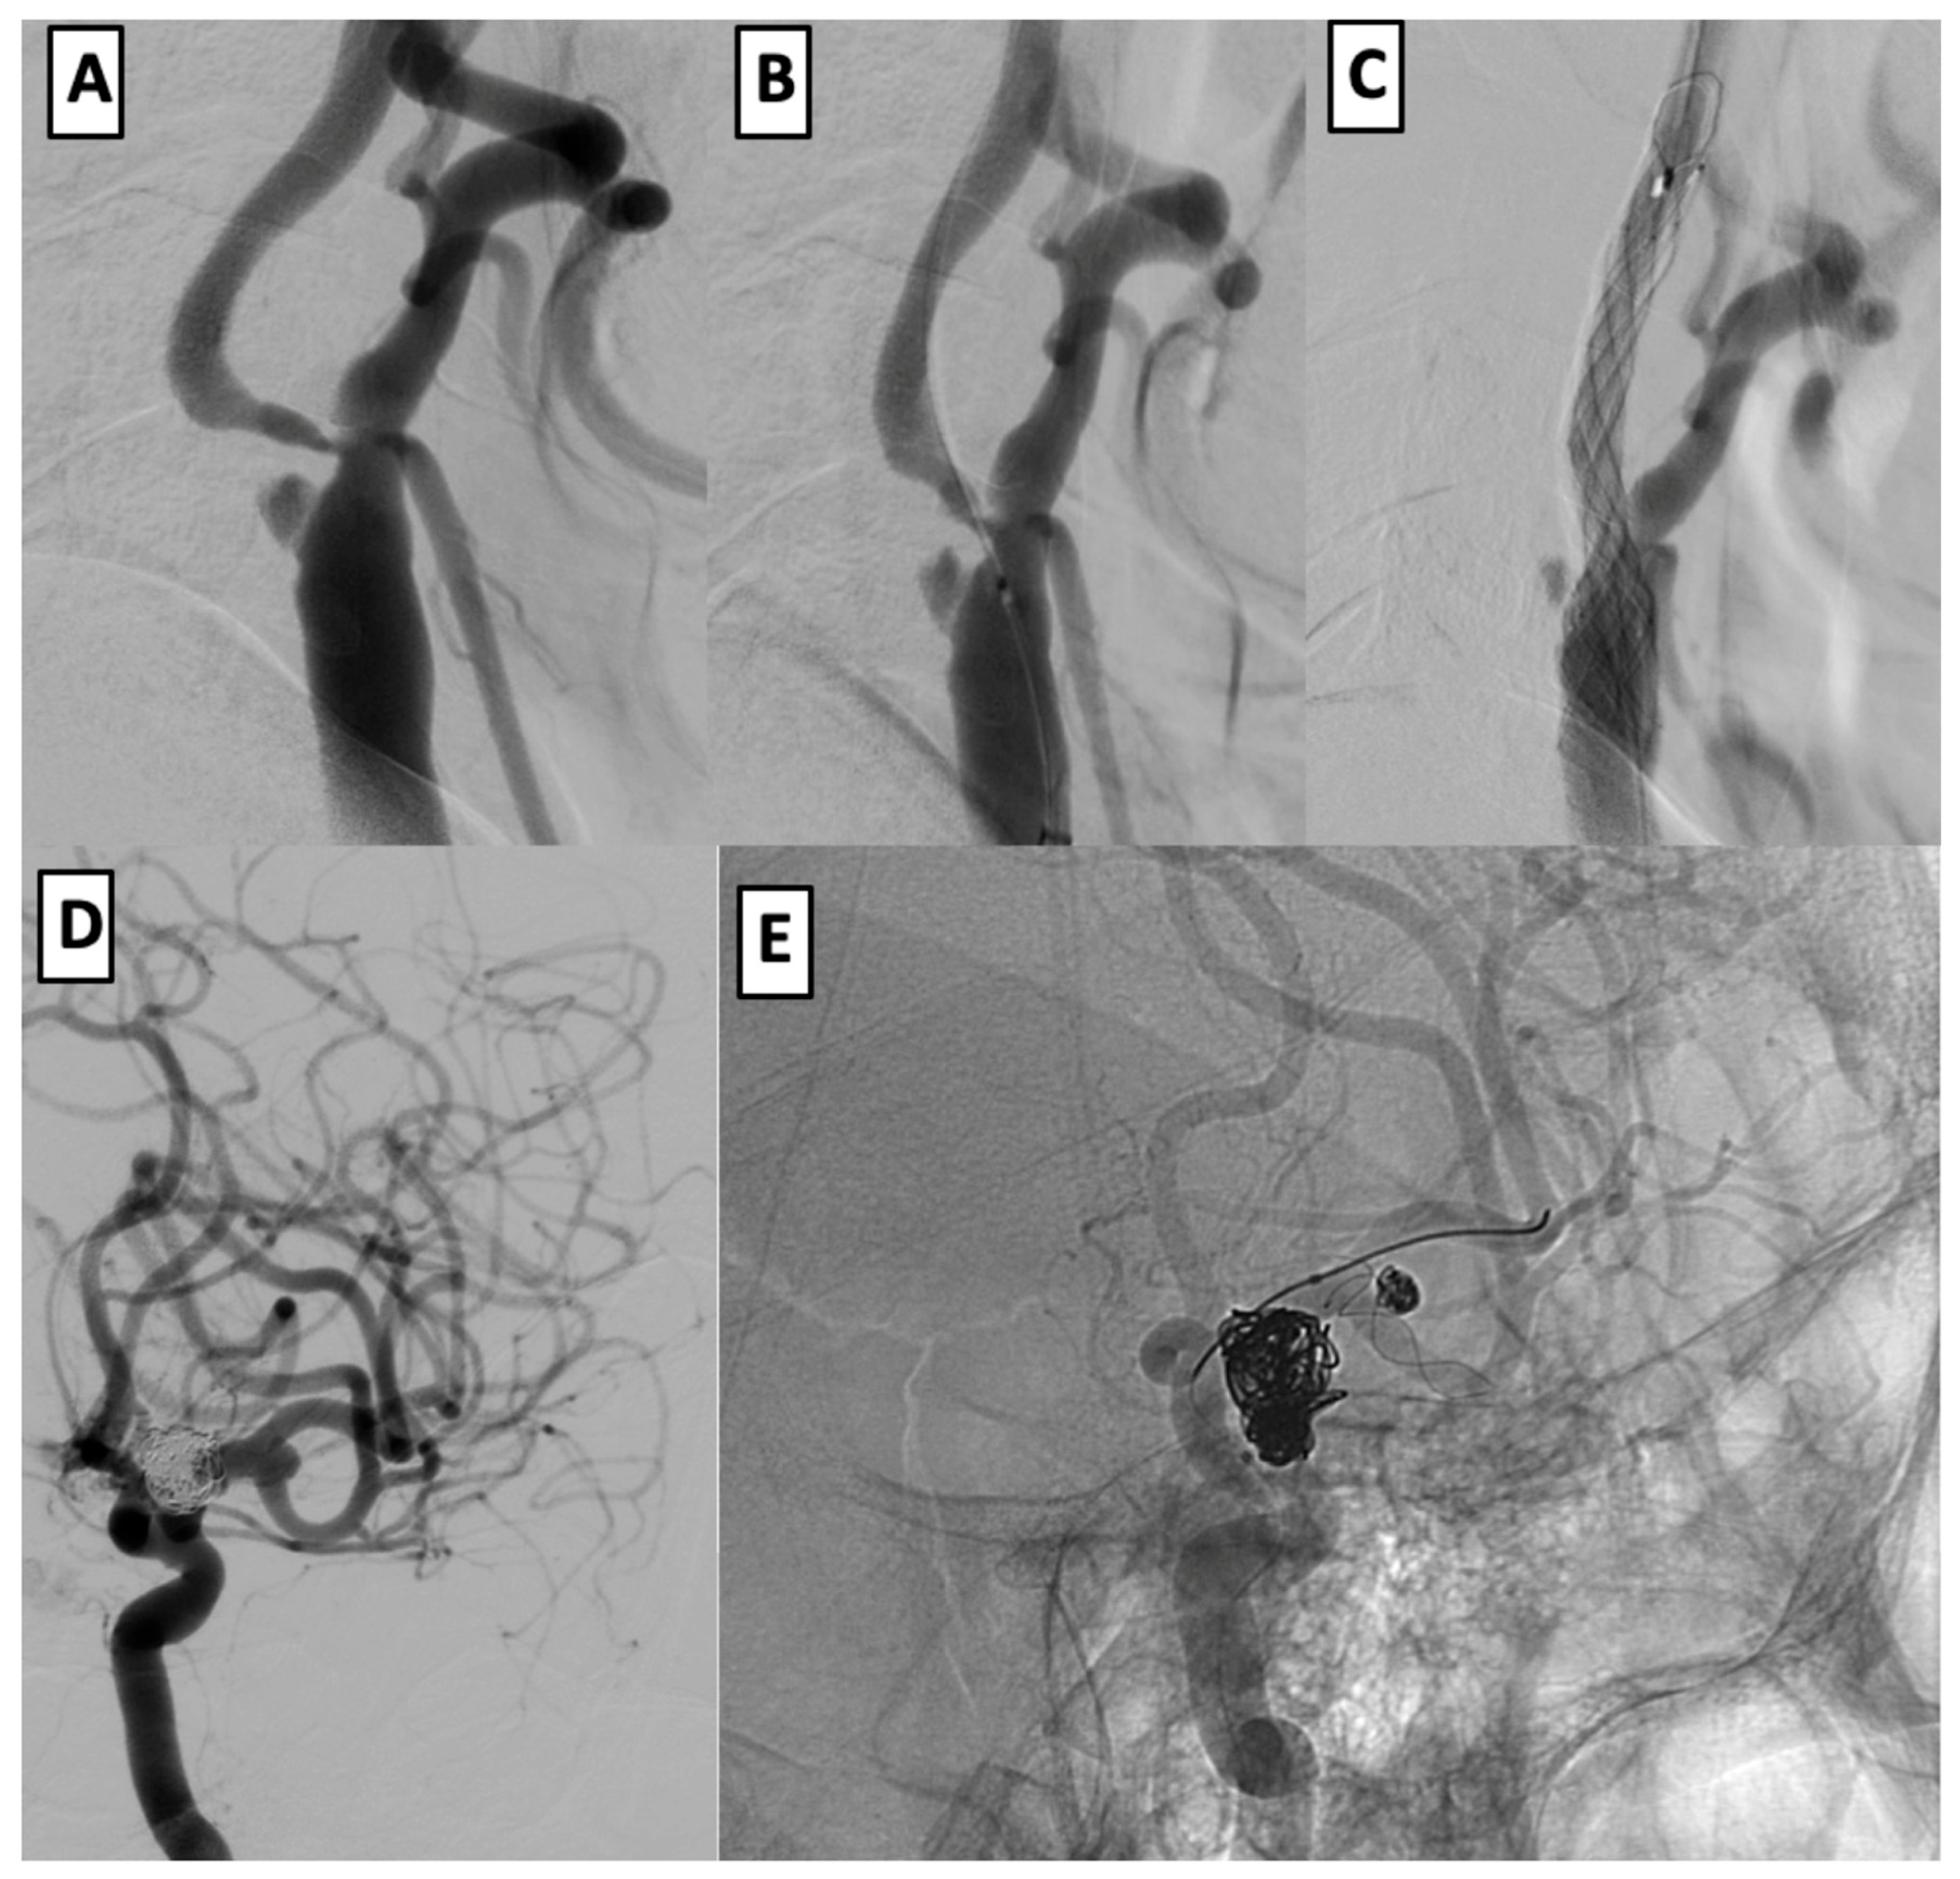

3.6. Case Examples